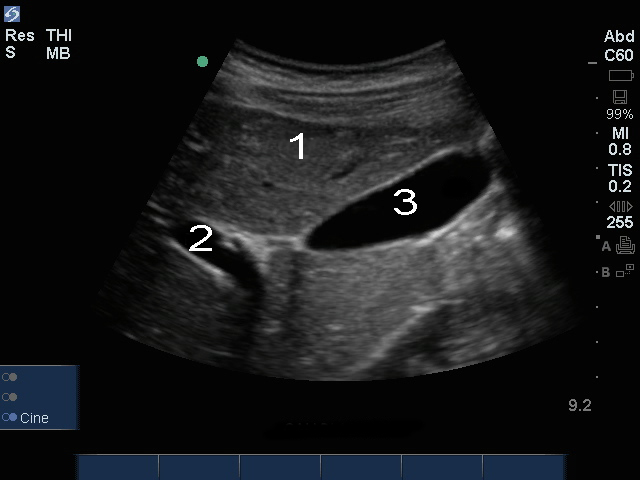

Bild: Gallenblase, Pfortader

Leber

Pfortader (PA)

Gallenblase (GB)